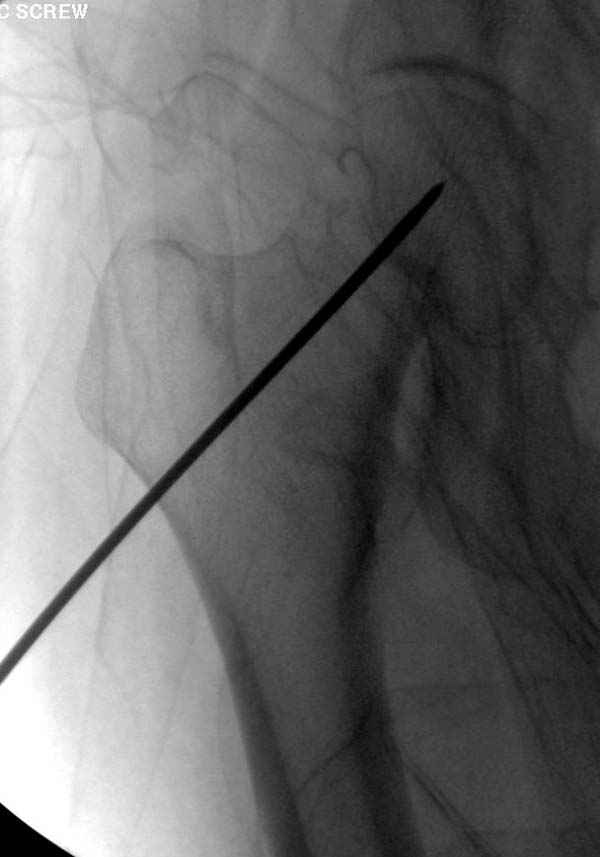

Профилактику дальнейшего раскола неполного перелома шейки провели тремя канюлированными шурупами.

На второй день после выписки упал дома. Снимки приложены. Коллеги рекомендуют удаление шурупа и вытяжение. Что делать?